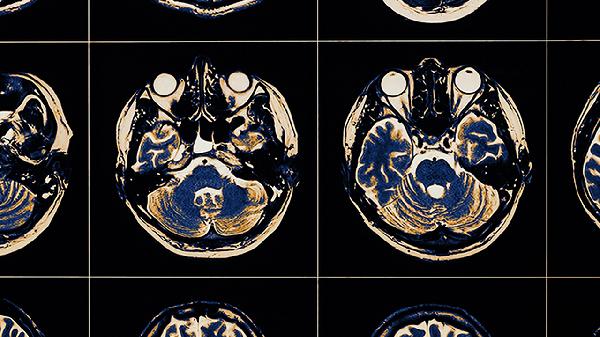

老年人大腦萎縮后期癥狀主要表現(xiàn)為認(rèn)知功能嚴(yán)重衰退、運動功能障礙、精神行為異常、語言能力喪失及生活完全不能自理。癥狀發(fā)展通常經(jīng)歷輕度記憶減退到全面功能喪失的過程。

后期患者會出現(xiàn)嚴(yán)重記憶力喪失,無法辨認(rèn)親友或熟悉環(huán)境,時間地點定向力完全缺失。計算能力和邏輯思維明顯受損,可能伴隨失認(rèn)癥和失用癥,部分患者會出現(xiàn)科薩科夫綜合征等器質(zhì)性精神障礙。這種情況與大腦皮層廣泛性萎縮及海馬區(qū)神經(jīng)元大量死亡有關(guān)。

患者多表現(xiàn)為肌張力增高、步態(tài)異常和姿勢反射喪失,后期常出現(xiàn)帕金森樣癥狀如靜止性震顫和運動遲緩。部分患者因小腦萎縮導(dǎo)致共濟(jì)失調(diào),最終可能完全喪失行走能力,需長期臥床。這些癥狀與基底節(jié)區(qū)、小腦浦肯野細(xì)胞退化密切相關(guān)。

常見激越、攻擊行為、幻覺妄想等精神癥狀,夜間癥狀加重呈現(xiàn)日落綜合征。情感控制能力喪失,可能出現(xiàn)病理性哭笑或情感淡漠。額顳葉萎縮患者更易出現(xiàn)人格改變和行為失控,這與神經(jīng)遞質(zhì)系統(tǒng)紊亂及邊緣系統(tǒng)損傷有關(guān)。

從找詞困難發(fā)展為完全失語,包括表達(dá)性失語、感受性失語和混合性失語。部分患者僅能發(fā)出無意義音節(jié),或出現(xiàn)模仿語言和重復(fù)語言。優(yōu)勢半球顳葉及布洛卡區(qū)萎縮是主要病理基礎(chǔ),晚期可能出現(xiàn)緘默癥。

最終階段患者完全喪失基本生活能力,包括進(jìn)食、穿衣、如廁等日?;顒泳杷藚f(xié)助??赡艹霈F(xiàn)吞咽困難導(dǎo)致吸入性肺炎,長期臥床易引發(fā)壓瘡和深靜脈血栓。這種情況反映大腦多系統(tǒng)功能全面衰竭,通常伴隨多器官功能退化。